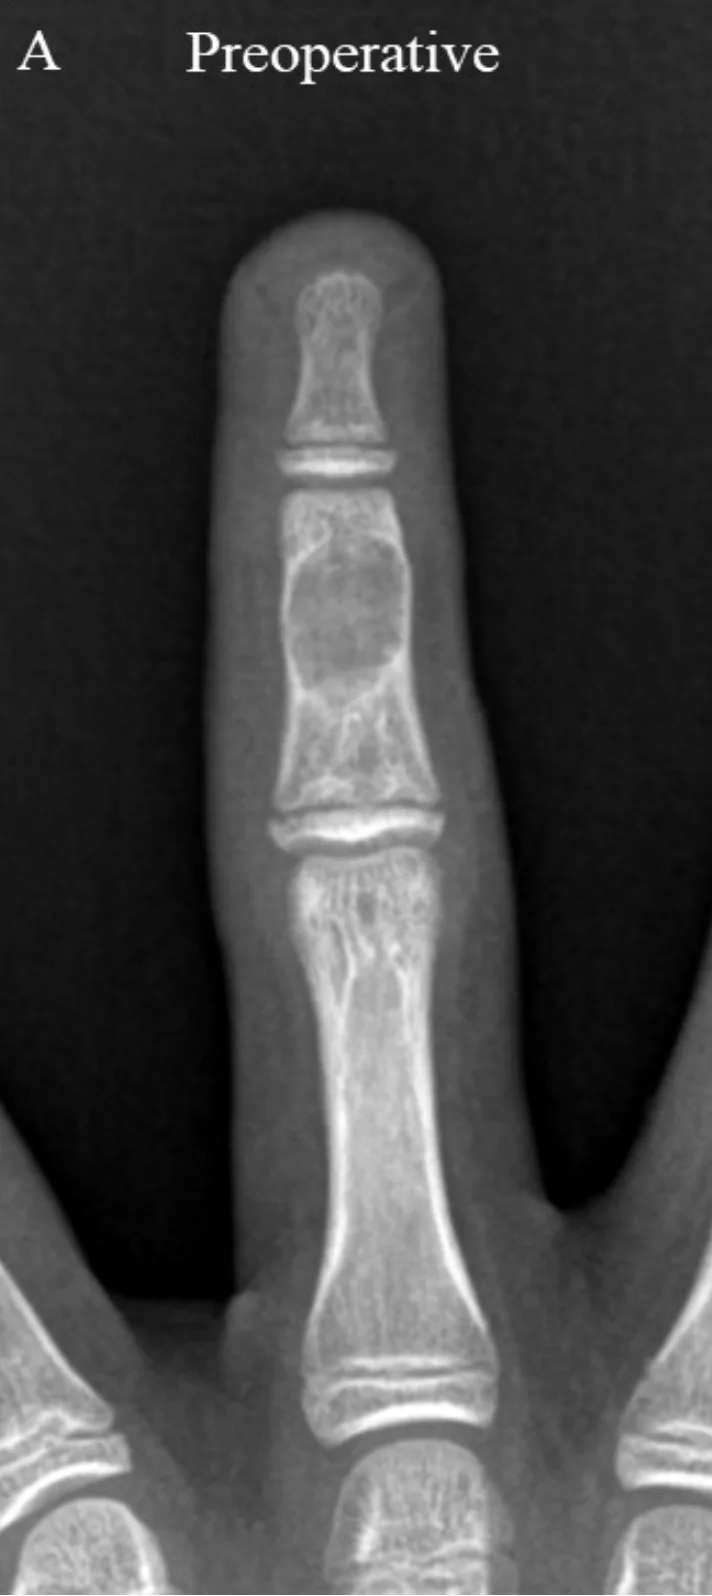

骨が透けるように壊されて, 壁の骨(皮質骨)が薄くなってふくらんでいます.

午後は, 薬指の中節骨に生じた内軟骨腫という良性骨腫瘍の手術でした.

4年前に腫瘍を削り取る手術をおこなったのですが, 再発したため, 2回目の手術.